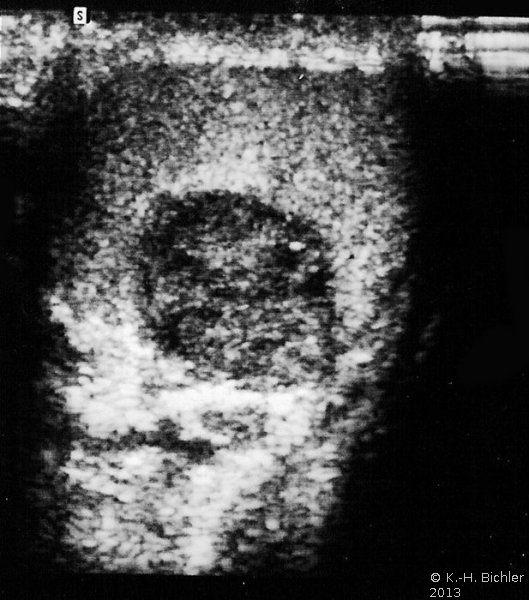

Noduläre Leydig-Zell-Hyperplasien sind in der Sonographie ebenfalls als umschriebene Tumoren erkennbar (Abbildung 7).

Bei dem jungen Erwachsenen bestand ein männlicher Pseudohermaphroditismus (Reifenstein-Syndrom) mit deutlich verkleinerten Hoden, Hypospadie und Gynäkomastie. Sonographisch fiel im rechten Hoden ein hypodenses tumorverdächtiges Areal auf (Abbildung 1). Die daraufhin erfolgte Hodenfreilegung und Biopsie ergaben zunächst die Diagnose Leydig-Zell-Tumor, nach weiteren Untersuchungen noduläre Leydig-Zell-Hyperplasie (Abbildung 9).